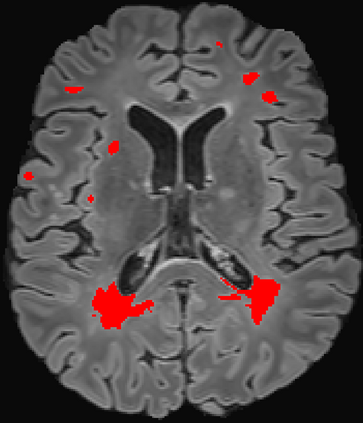

Assessment of lesions and their longitudinal progression from brain magnetic resonance (MR) images plays a crucial role in diagnosing and monitoring multiple sclerosis (MS). Machine learning models have demonstrated a great potential for automated MS lesion segmentation. Training such models typically requires large-scale high-quality datasets that are consistently annotated. However, MS imaging datasets are often small, segregated across multiple sites, with different formats (cross-sectional or longitudinal), and diverse annotation styles. This poses a significant challenge to train a unified MS lesion segmentation model. To tackle this challenge, we present SegHeD, a novel multi-dataset multi-task segmentation model that can incorporate heterogeneous data as input and perform all-lesion, new-lesion, as well as vanishing-lesion segmentation. Furthermore, we account for domain knowledge about MS lesions, incorporating longitudinal, spatial, and volumetric constraints into the segmentation model. SegHeD is assessed on five MS datasets and achieves a high performance in all, new, and vanishing-lesion segmentation, outperforming several state-of-the-art methods in this field.